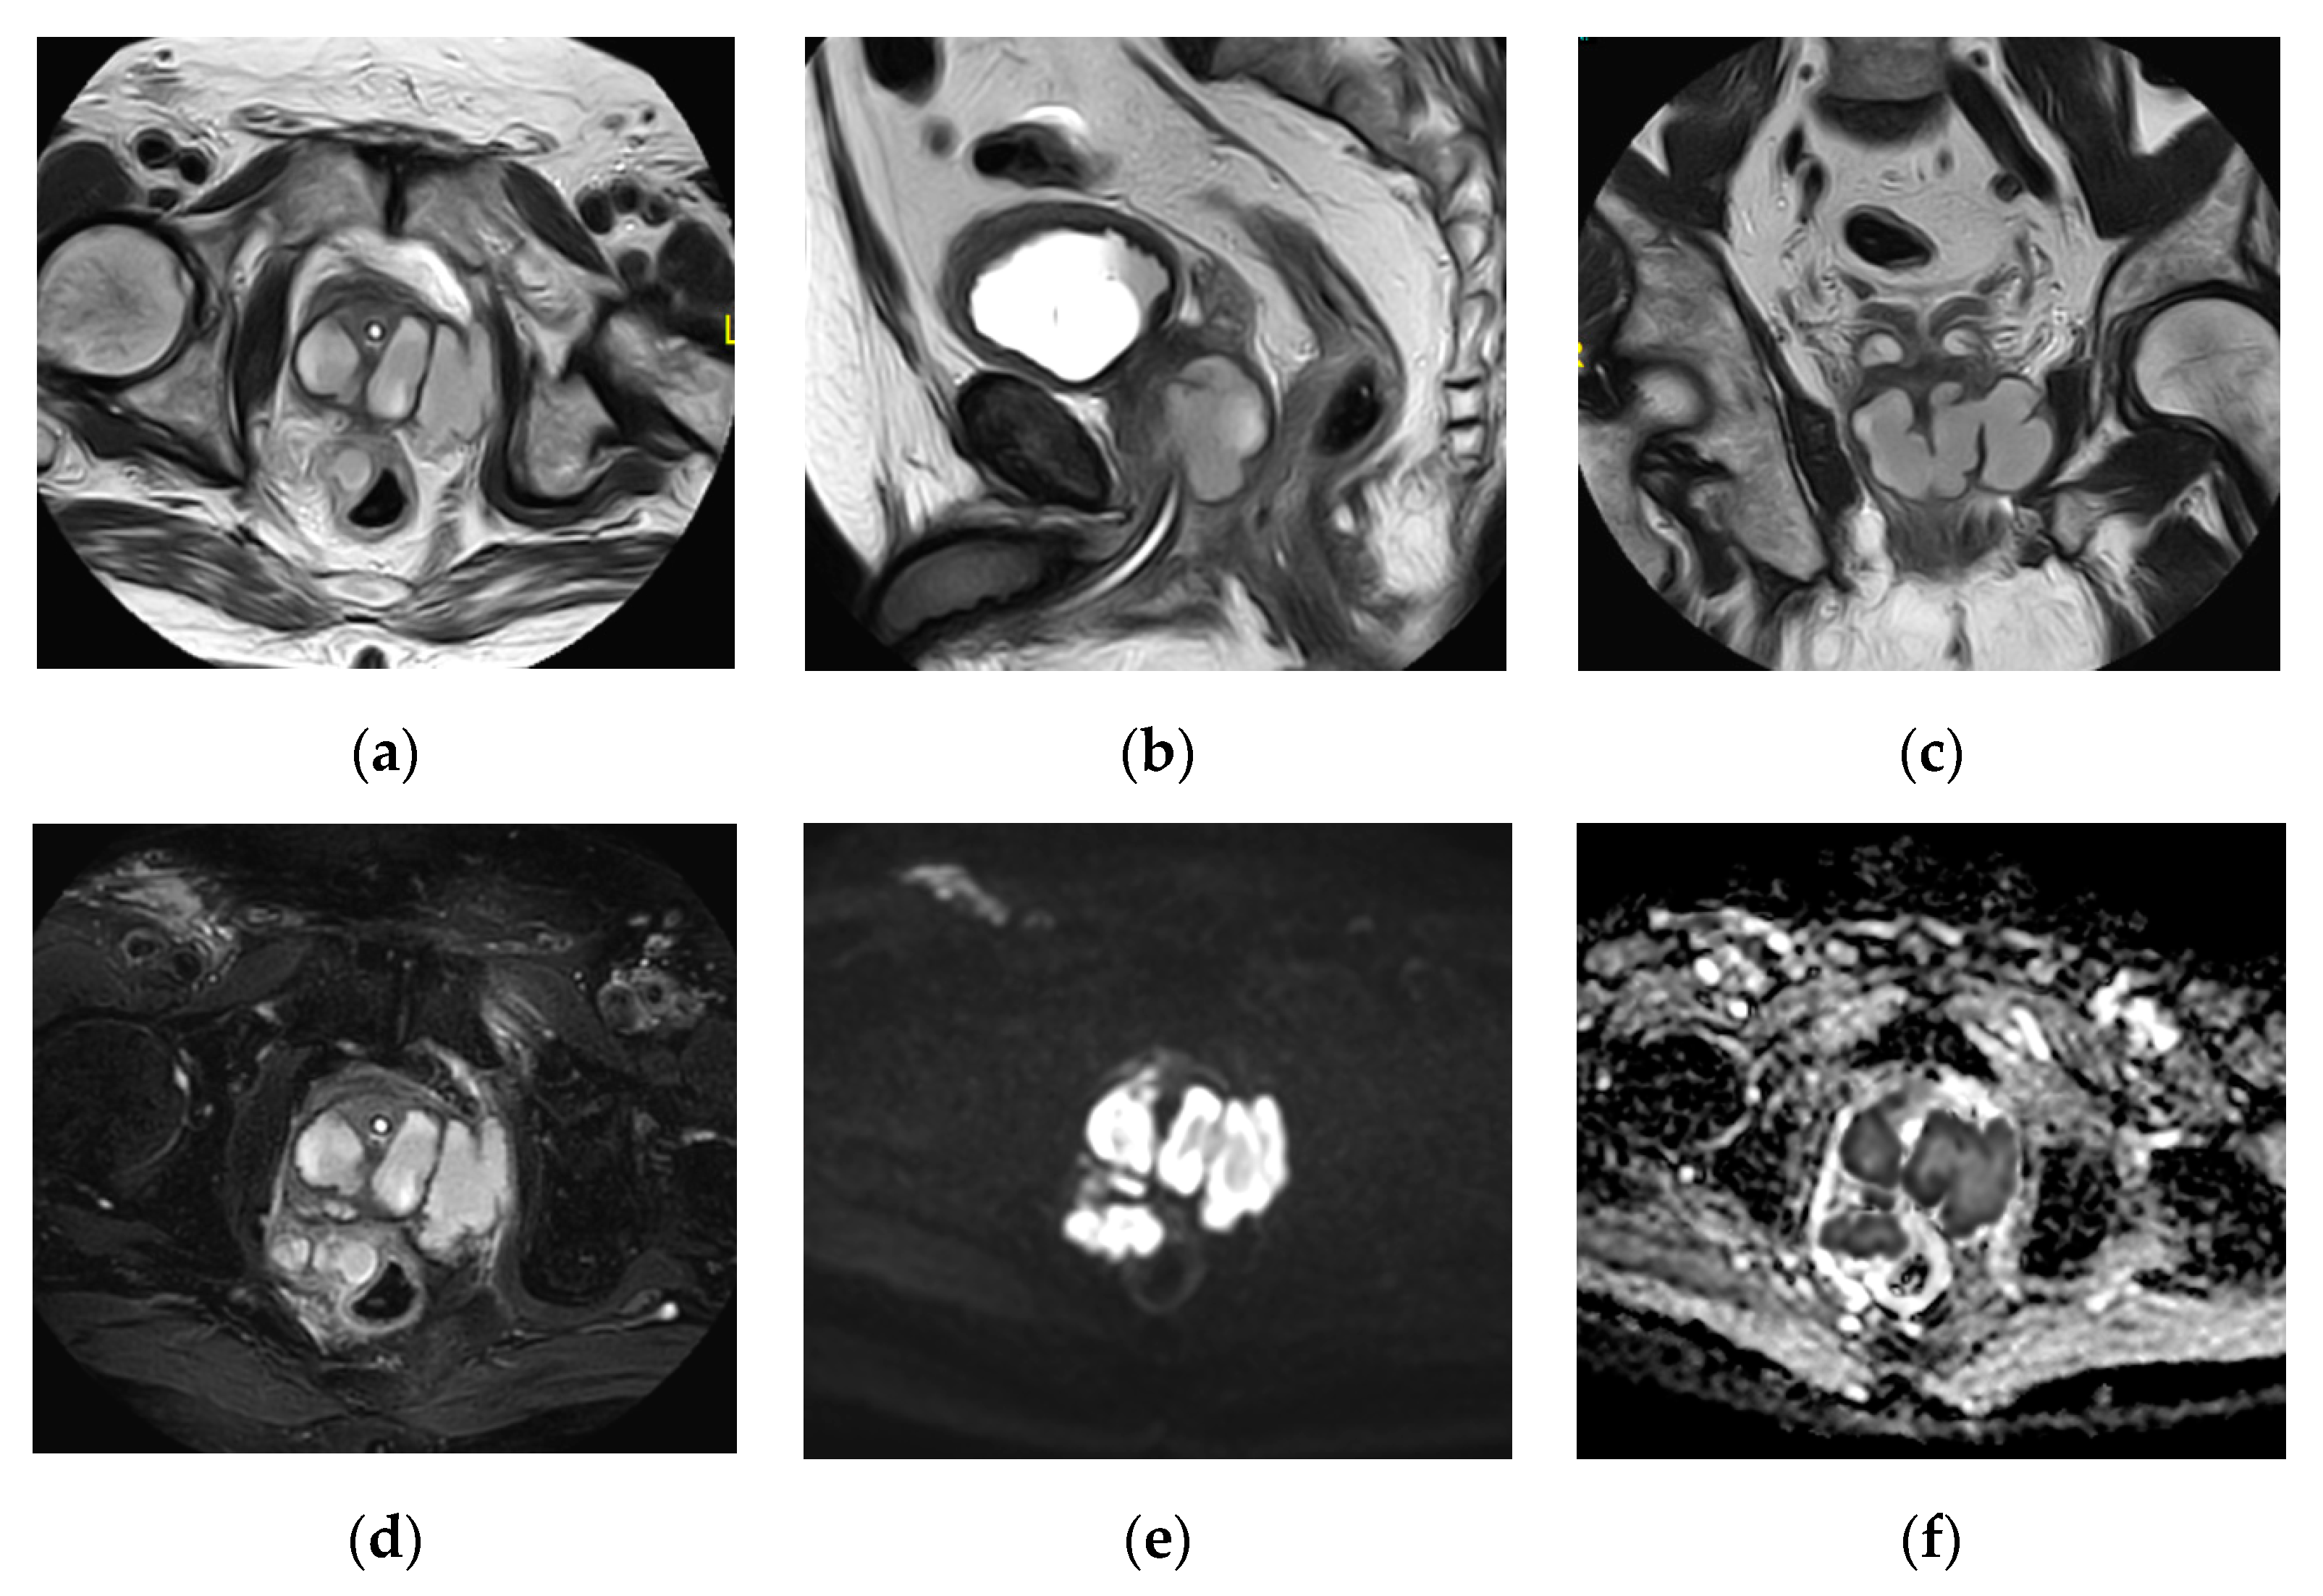

2.15. Acute Bacterial Prostatitis and Prostatic Abscess

- Ren, J.; Huang, X.; Wang, H.; Liu, H.; Ren, F.; Zhang, Z.; Yang, Y.; Yin, H.; Huan, Y. Prostatic abscess and seminal vesicle abscess: MRI findings and quantitative analysis of apparent diffusion coefficient values. Radiol. Infect. Dis. 2015, 2, 27–32. [Google Scholar] [CrossRef]

| Prostatic abscess | Non enhancing fluid collection with peripheral or septal enhancement and non-enhancing central fluid. Possible extraprostatic extension |